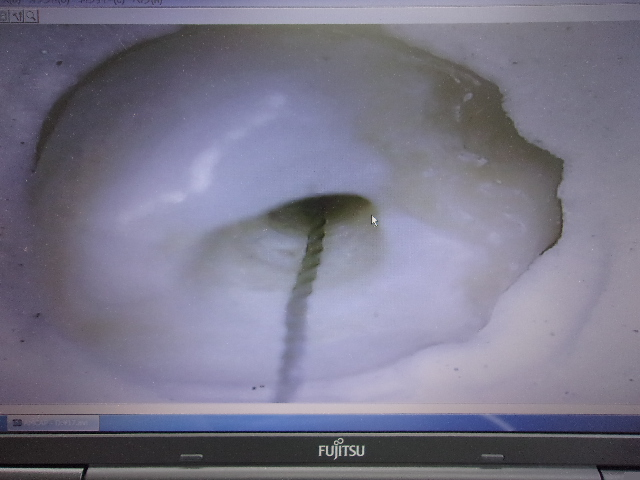

歯の根管の検索も考慮できます(模型による説明)New!